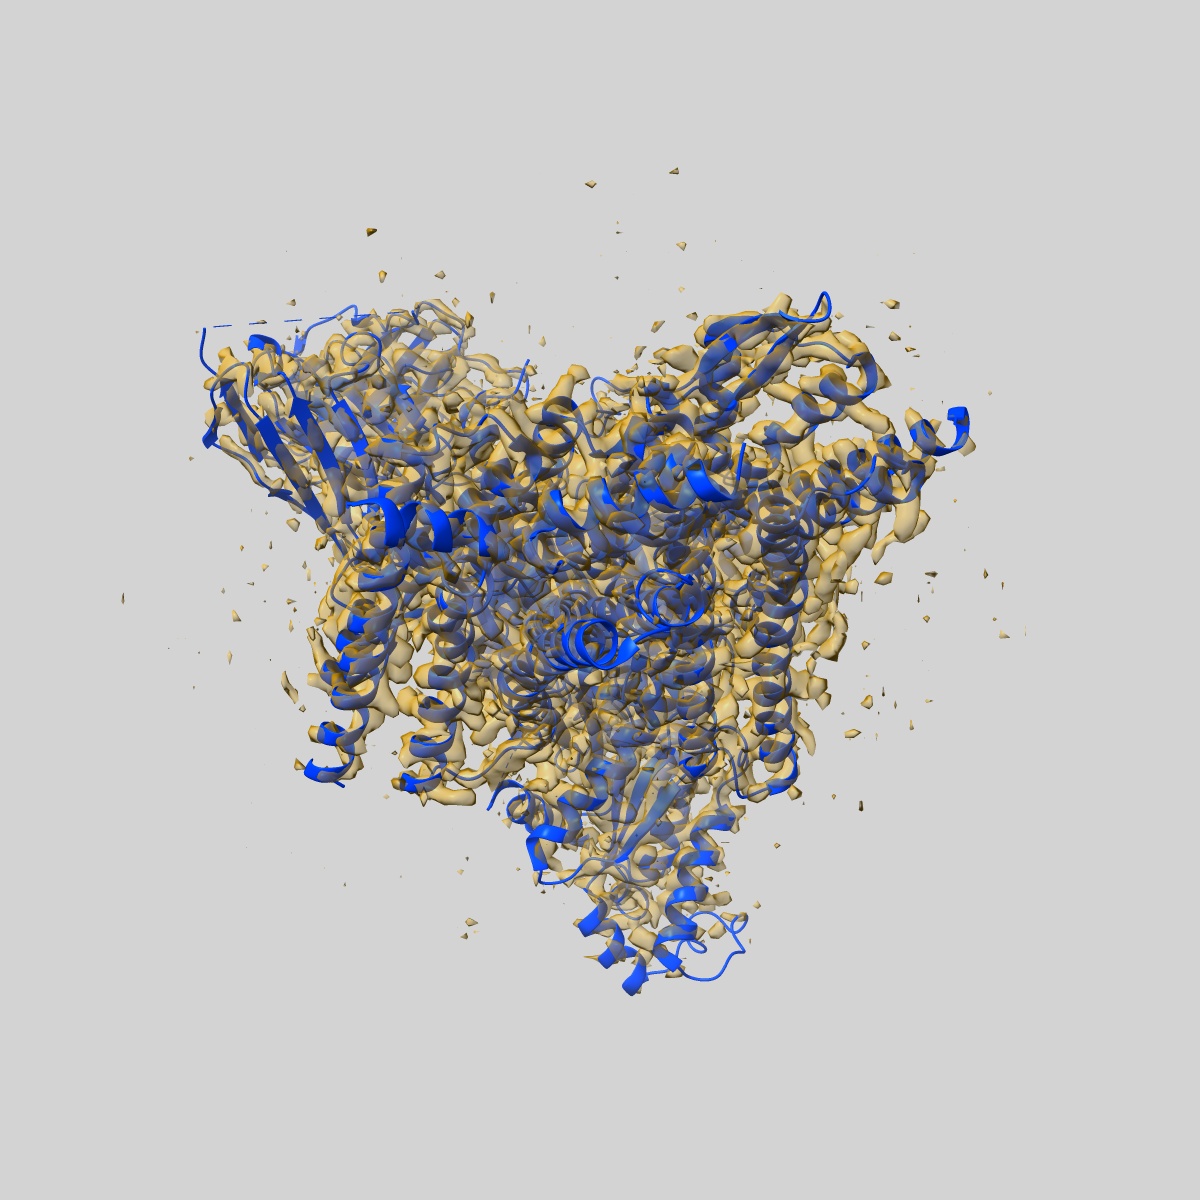

Morphine-bound mu-opioid receptor-Gi complex

Single-particle3.2 Å

Sample: fentanyl bound mu-opioid receptor-G protein complex

Fitted models: 8ef6

Molecular recognition of morphine and fentanyl by the human mu-opioid receptor.

(2022) Cell , 185 , 4361 - 4375.e19